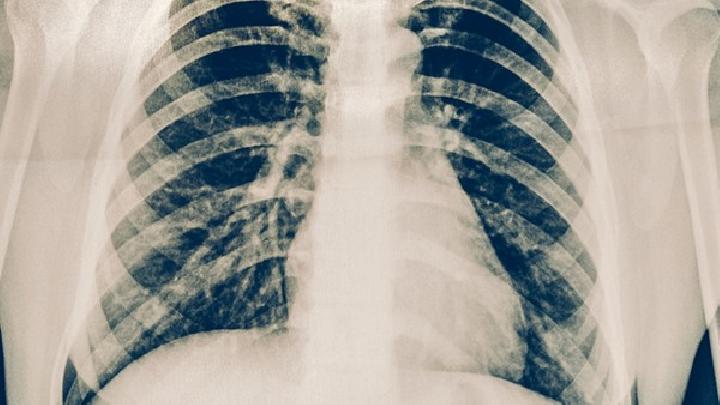

放射性肺炎

放射性肺炎是由什么原因引起的?